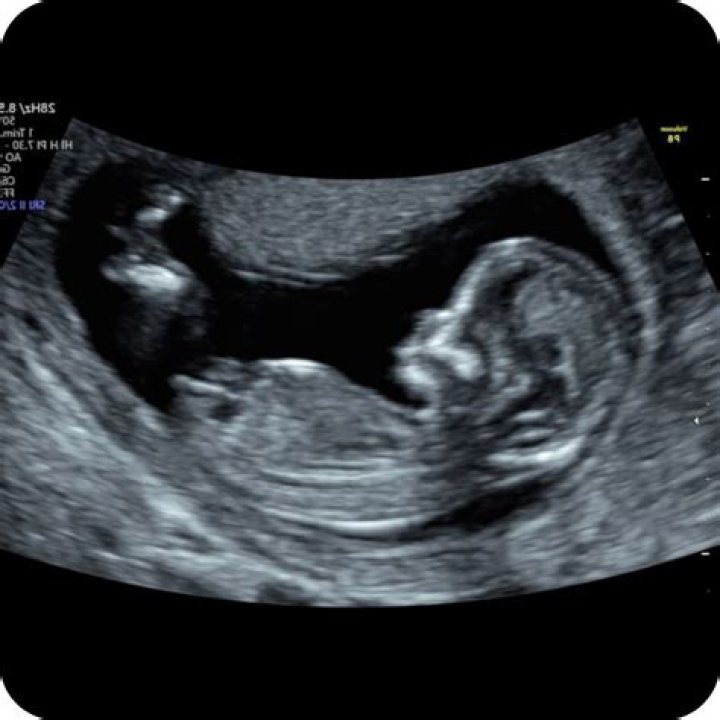

How big is a 12 week scan

At 12 weeks, the foetus is now about the size of a passion fruit, measuring close to 5.5 cm, crown to rump, and weighing approximately 18 grams.

What can I expect at my 12 week ultrasound?

Basic anatomy is visible on the 12-14 week ultrasound. Your medical provider can see if the heart has four chambers; if the brain has two hemispheres; and if the baby has eyes, limbs, lungs, a spine and a bladder, said Dr.

Can a 12 week ultrasound detect Down syndrome?

The 12-week ultrasound allows your healthcare provider to check how your baby is developing and screen for conditions like Down syndrome. Your practitioner can also determine your due date and how many babies you are carrying with this scan.